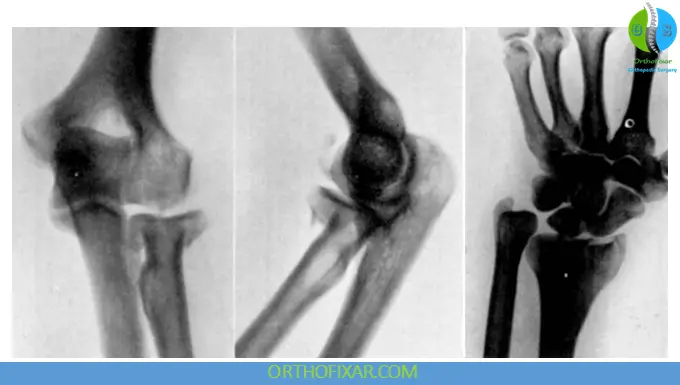

Classification (Modified Mason Classification)

- Type I: Nondisplaced fractures

- Type II: Displaced marginal fractures

- Type III: Comminuted fractures of the entire head

- Type IV: Radial head fracture with elbow dislocation